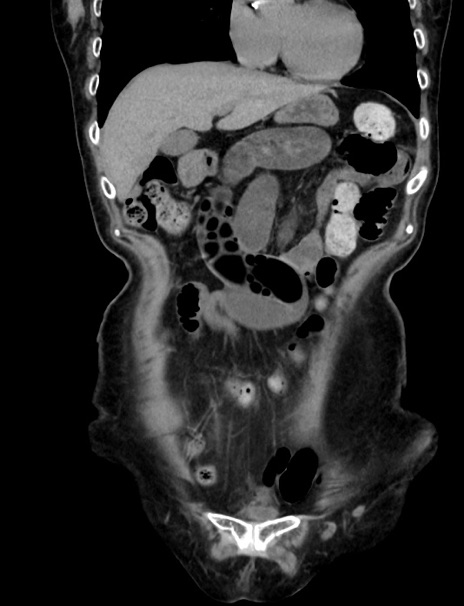

症例33(冠状断像)

【症例】70歳代 女性

【主訴】心窩部痛

【現病歴】延髄病変の精査・加療にて神経内科入院中。本日より心窩部痛あり。

【身体所見】右下腹部を中心に圧痛と反跳痛あり。